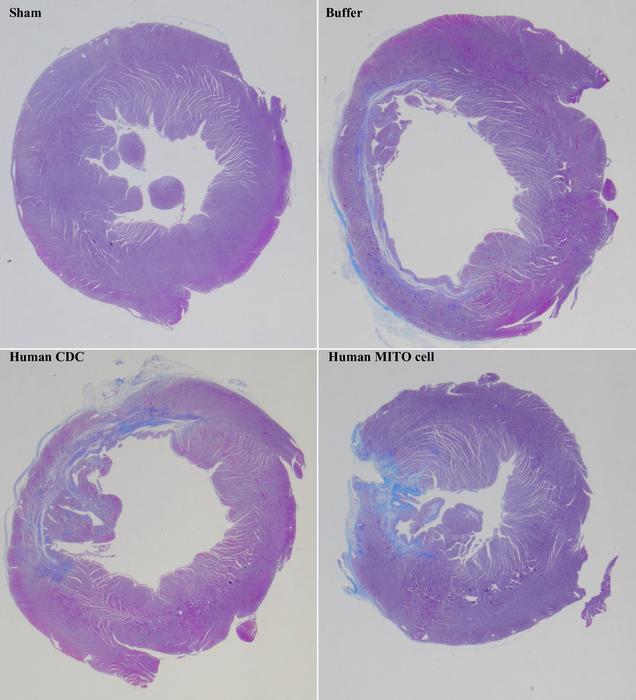

Yamada and his group have previously developed a drug delivery system called MITO-Porter, which targets mitochondria within cells. In the current study, they used MITO-Porter to deliver Coenzyme Q 10 (CoQ 10 ) to human cardiosphere-derived cells (CDCs), activating their mitochondria (human MITO cells). When these human MITO cells were transplanted into a rat model of myocardial ischemia-reperfusion injury, cardiac function significantly improved. A remarkable ability to suppress myocardial fibrosis was also demonstrated, which could prevent incorrect healing of heart tissue.